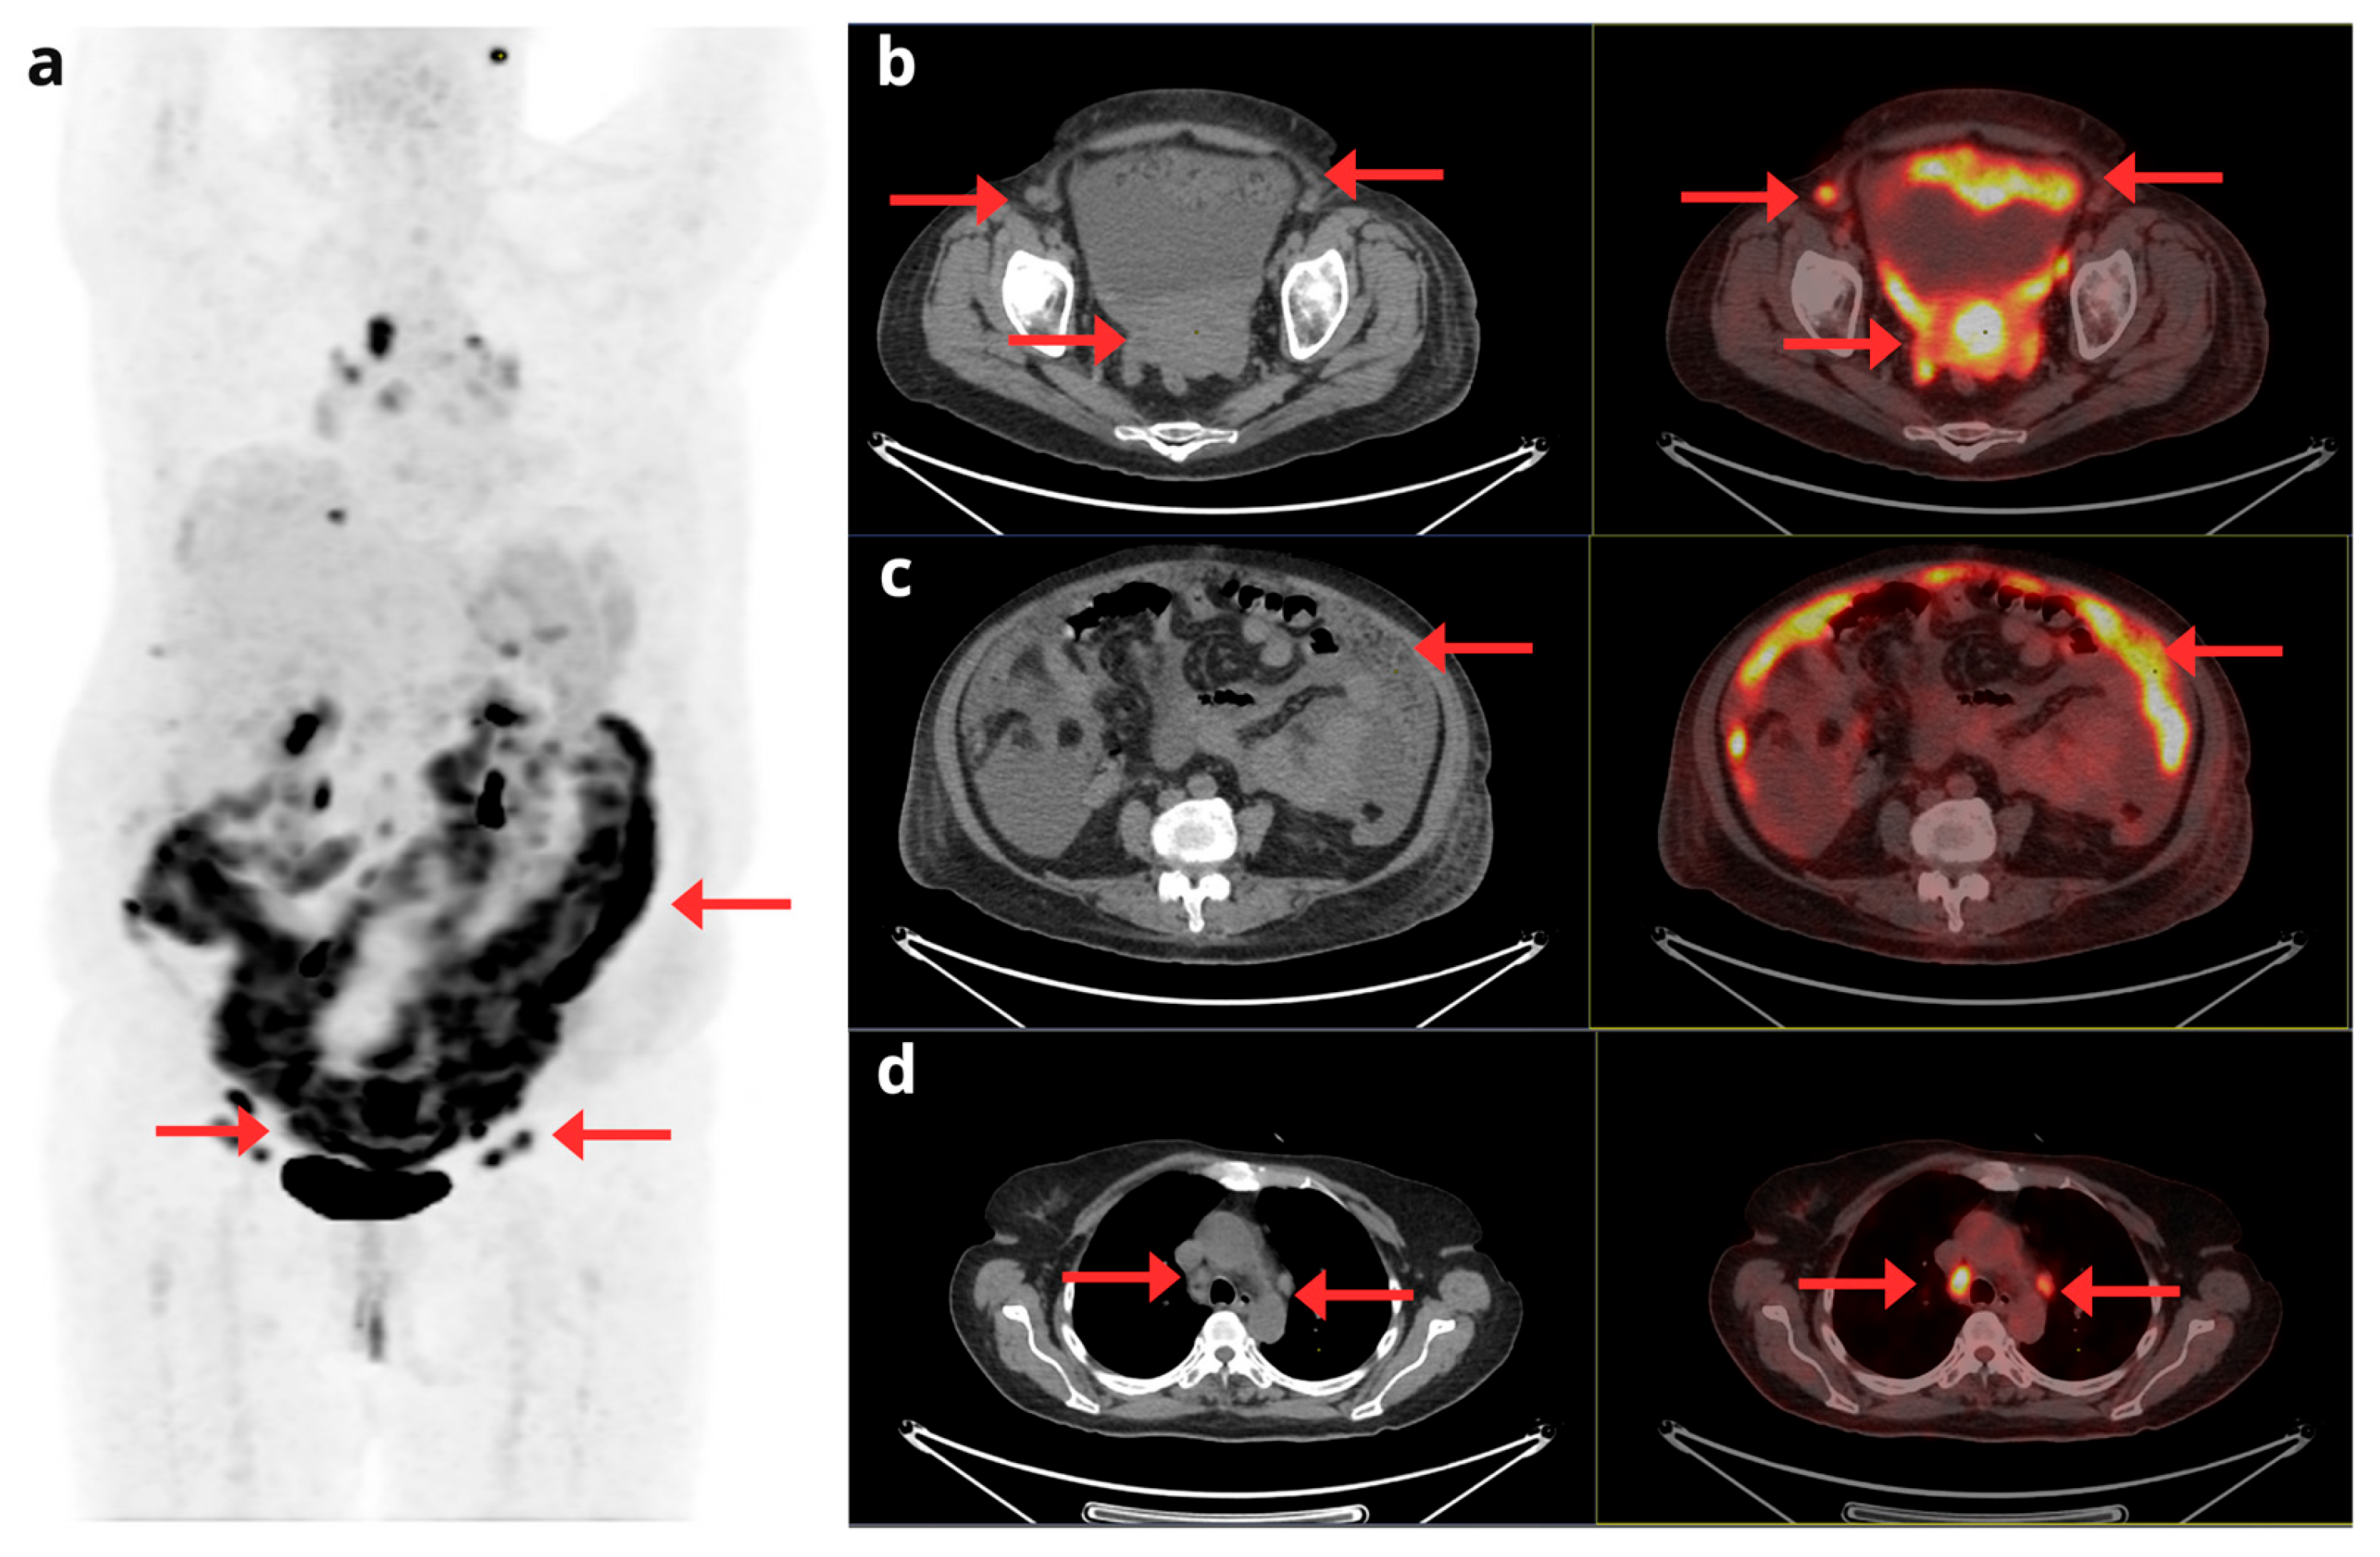

- Kurra, V.; Krajewski, K.M.; Jagannathan, J.; Giardino, A.; Berlin, S.; Ramaiya, N. Typical and Atypical Metastatic Sites of Recurrent Endometrial Carcinoma. Cancer Imaging 2013, 13, 113–122. [CrossRef]

- Kadkhodayan, S.; Shahriari, S.; Treglia, G.; Yousefi, Z.; Sadeghi, R. Accuracy of 18-F-FDG PET Imaging in the Follow up of Endometrial Cancer Patients: Systematic Review and Meta-Analysis of the Literature. Gynecol. Oncol. 2013, 128, 397–404. [CrossRef]

- Kirchner, J.; Sawicki, L.M.; Suntharalingam, S.; Grueneisen, J.; Ruhlmann, V.; Aktas, B.; Deuschl, C.; Herrmann, K.; Antoch, G.; Forsting, M.; et al. Whole-Body Staging of Female Patients with Recurrent Pelvic Malignancies: Ultra-Fast 18F-FDG PET/MRI Compared to 18F-FDG PET/CT and CT. PLoS One 2017, 12, e0172553. [CrossRef]

- Zheng, M.; Xie, D.; Pan, C.; Xu, Y.; Yu, W. Diagnostic Value of 18F-FDG PET/MRI in Recurrent Pelvis Malignancies of Female Patients: A Systematic Review and Meta-Analysis. Nucl Med Commun 2018, 39, 479–485. [CrossRef]

- Chao, A.; Chang, T.-C.; Ng, K.-K.; Hsueh, S.; Huang, H.-J.; Chou, H.-H.; Tsai, C.-S.; Yen, T.-C.; Wu, T.-I.; Lai, C.-H. 18F-FDG PET in the Management of Endometrial Cancer. Eur J Nucl Med Mol Imaging 2006, 33, 36–44. [CrossRef]

- Belhocine, T.; De Barsy, C.; Hustinx, R.; Willems-Foidart, J. Usefulness of 18F-FDG PET in the Post-Therapy Surveillance of Endometrial Carcinoma. Eur J Nucl Med 2002, 29, 1132–1139. [CrossRef]

- Park, J.-Y.; Kim, E.N.; Kim, D.-Y.; KiM, J.-H.; Kim, Y.-M.; Kim, Y.-T.; Nam, J.-H. Clinical Impact of Positron Emission Tomography or Positron Emission Tomography/Computed Tomography in the Posttherapy Surveillance of Endometrial Carcinoma: Evaluation of 88 Patients. International Journal of Gynecological Cancer 2008, 18, 1332–1338. [CrossRef]

- Sawicki, L.M.; Kirchner, J.; Grueneisen, J.; Ruhlmann, V.; Aktas, B.; Schaarschmidt, B.M.; Forsting, M.; Herrmann, K.; Antoch, G.; Umutlu, L. Comparison of 18F–FDG PET/MRI and MRI Alone for Whole-Body Staging and Potential Impact on Therapeutic Management of Women with Suspected Recurrent Pelvic Cancer: A Follow-up Study. Eur J Nucl Med Mol Imaging 2018, 45, 622–629. [CrossRef]